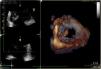

We present the case of a 65-year-old man with a history of high blood pressure. During a follow-up appointment, a holosystolic murmur, III/VI, radiating to the armpit was detected. He was cardiovascularly asymptomatic. A complete echocardiogram was performed, with the following findings: severely dilated left atrium; mitral valve with an aneurysmal lesion at the A2 scallop (Figure 1) causing severe regurgitation with an eccentric jet. There was systolic flow reversal in the pulmonary veins. The mechanism of regurgitation is Carpentier II. The rest of the valves had normal morphology and function, biventricular function, large vessels, and the pericardium. There was an intermediate probability of pulmonary hypertension. Findings were confirmed and the lesion was further characterized using transesophageal echocardiogram and three-dimensional reconstruction (Figure 2).